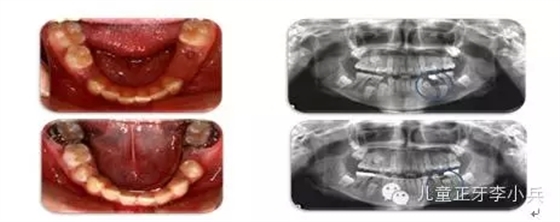

1. 兒童牙病的治療與錯合畸形的預防:兒童齲病造成牙冠橫徑變短、乳牙早失、磨牙前移。兒童根尖周病影響恒牙發(fā)育及萌出異常,阻生。兒童牙病治療、間隙維持能預防繼承恒牙的萌出異常。(圖2,病例一)

圖2 75深齲,34牙胚萌出異常,拔出75,舌弓間隙維持后,34萌出道自行調(diào)整萌出;